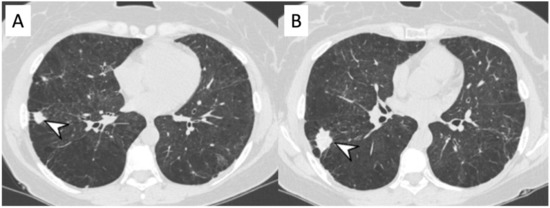

2.3. Microscopic Polyangiitis (MPA)

| MPA | GGOs due to hemorrhagic alveolitis (common); consolidation, nodules with centrilobular distribution (less common) |